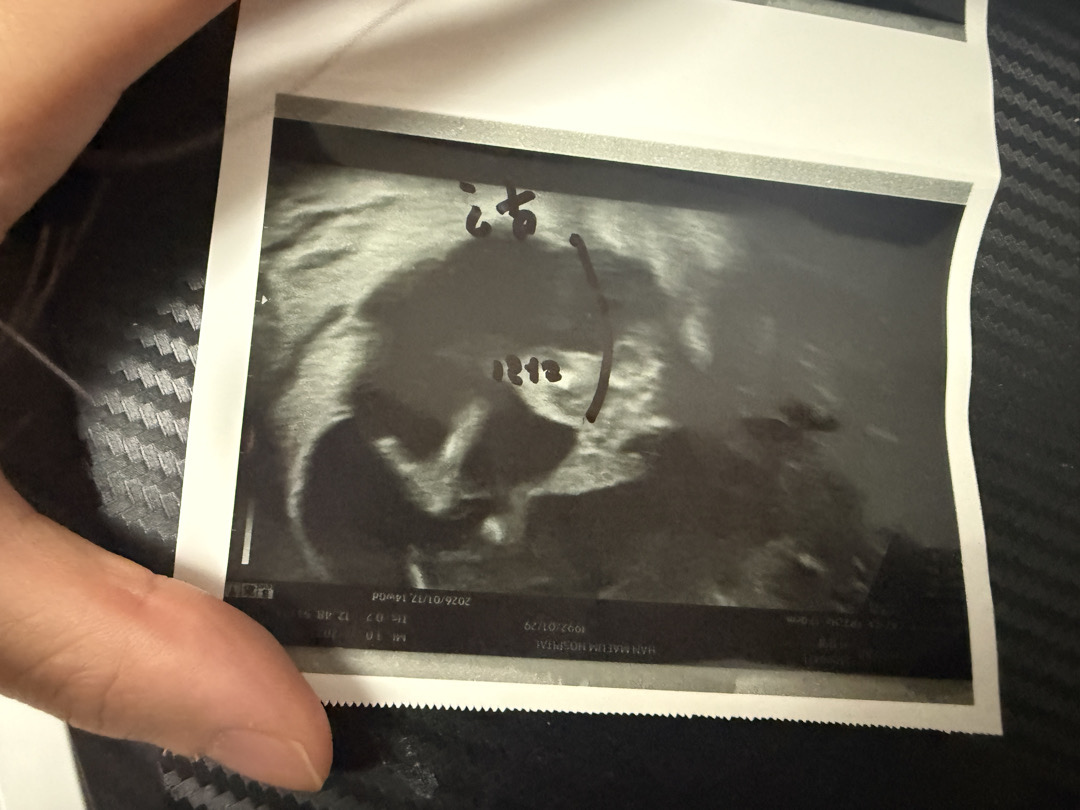

14주차 성별 궁금합니다

선생님은 보면서 딸이 70프로 인것같다고 하시는데 확실한걸까요?ㅋㅋ

딸인거 같아요 ㅎㅎㅎ